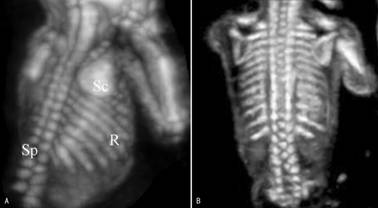

上述脊柱冠状面图像在脊柱的三维超声检查时显示的更为典型,并通过三维图像可以比较明确的计数椎体的数目(图2A),并且可以在胸部显示肋骨回声和数目(图2B)。

图2 胎儿脊柱(SP)和肋骨(R)三维显示